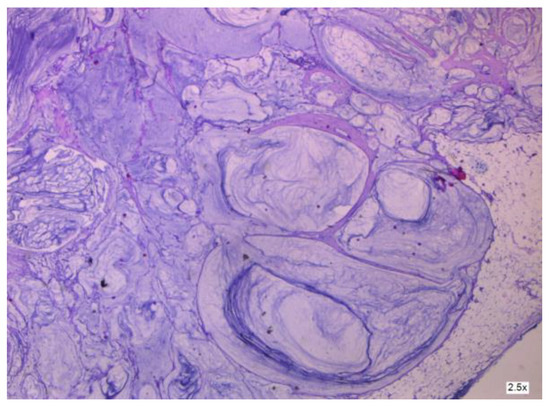

3.1.1. Mucinous Cystadenoma